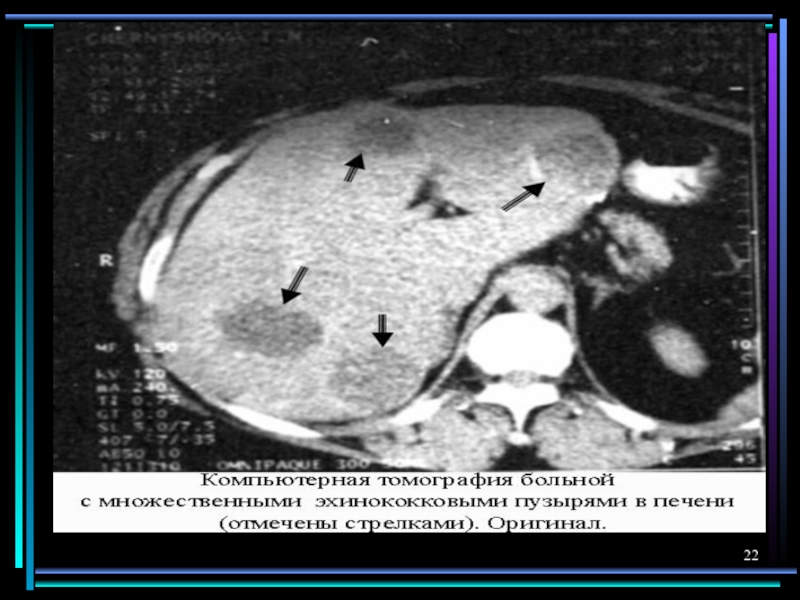

Слайд 19Поражение гепатопанкреато- дуоденальной системы

Эхинококкоз

Альвеококкоз

годы

Боли в правом подреберье и эпи-

астрии, гепатомегалия, желтуха,

обнаружение

кист на УЗИ, КТ, МРТ

Слайд 25Человек, больной эхинококкозом

Человек, больной эхинококкозом